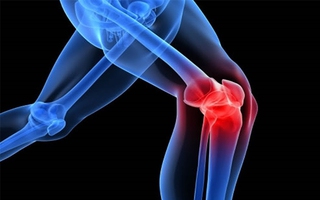

Khám miễn phí bệnh vảy nến

(NLĐO) - Vảy nến dễ nhầm với bệnh da khác, nếu không điều trị có thể gây tổn thương móng, khớp, mắt và làm tăng nguy cơ tim mạch, ung thư, trầm cảm.